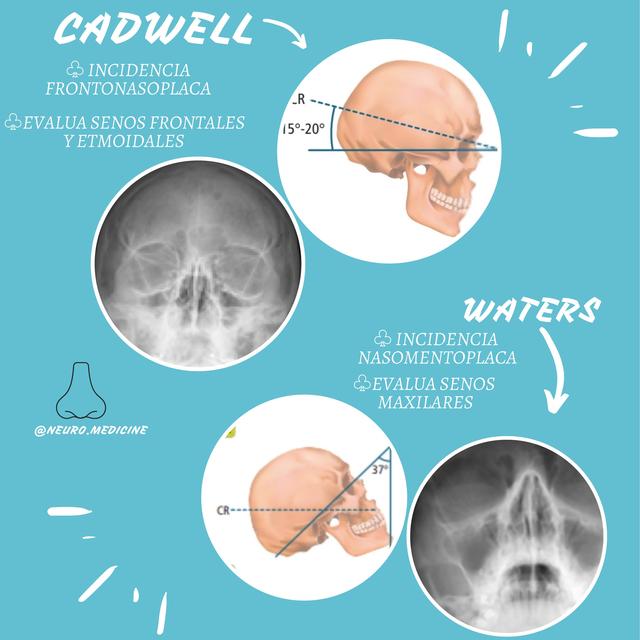

Download scientific diagram | Proyección de Waters: aumento de densidad de partes blandas de los senos maxilares (estrella) y presencia de masa en la faringe (flecha). from publication: Pólipo.. Citation, DOI, disclosures and article data. The Caldwell view is a caudally angled radiograph, with its posteroanterior projection allowing for minimal radiation to the orbits. This view may be used in imaging of the skull or facial bones depending on the clinical indications.

Proyección de Caldwell Wikiwand

Incidencias de CADWELL y WATERS NeuroMedicine uDocz

Descarga RX – Posiciones Radiológicas: https://play.google.com/store/apps/details?id=com.Tarter.RXPosicionesRadiolgicas&pcampaignid=web_sharehttps://apps.app.. Study with Quizlet and memorize flashcards containing terms like Proyección de Caldwell también llamada., Proyección de Waters también llamada., ¿Qué estructuras se aprecian mejor con la proyección de Caldwell? and more.